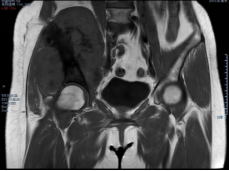

穿刺活检提示骨盆软骨肉瘤

3D打印假体设计

据主刀医师徐生林介绍,本例病例将整个右侧半骨盆Ⅰ+Ⅱ+Ⅲ+Ⅳ区(累及骶骨)进行整块切除,同时切除肿瘤覆盖的部分骶骨。3D打印假体所有骨接触界面均设计为骨整合结构,有利于骨长入和骨盆假体的永久稳定。耻、坐骨结构不规则,因此设计组配式结构,有利于术中操作,极大地方便了术中的假体安装。

3D打印技术的出现,使骨肿瘤的精准切除成为了可能,3D打印制造技术能够很好地适形匹配肿瘤切除后的骨结构,通过假体-骨接触面的特殊制造技术达到假体-骨整合,解决了骨肿瘤切除后大段骨关节缺损的重建问题,在生物力学重建和功能重建上比常规假体优势明显。3D打印假体使骨肿瘤切除重建进入“个性化、精准化、私人定制”时代。